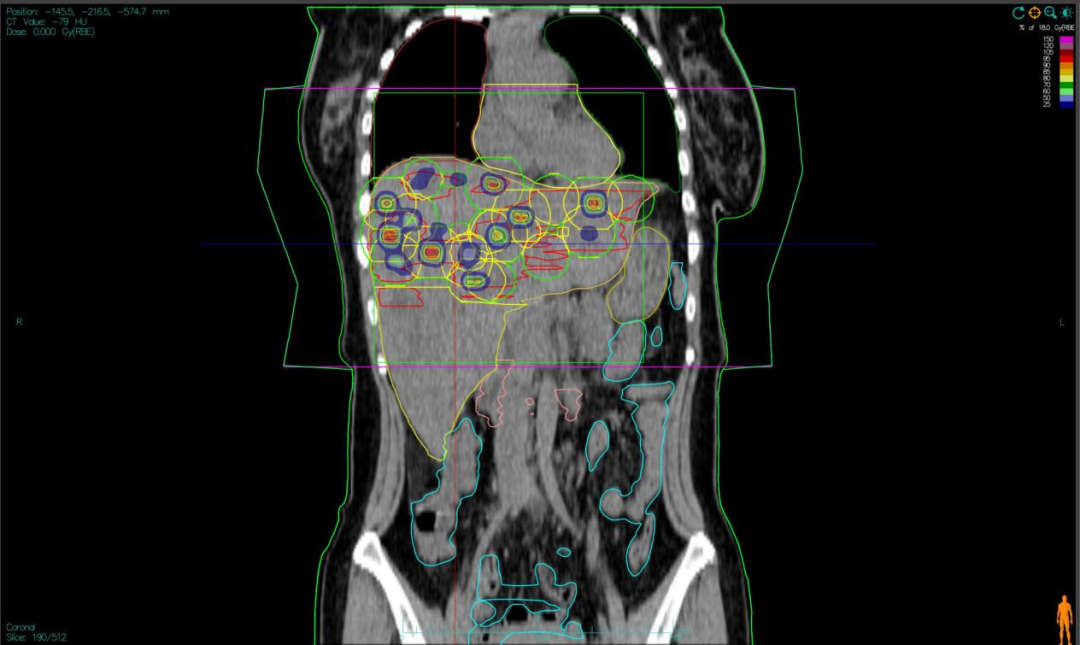

“双布拉格”,并非指代两个物理峰值,而是两大核心治疗理念的深度碰撞与融合。第一个“布拉格”,是物理学范畴的布拉格峰——重离子束流可在体内特定深度释放绝大部分能量,这一特性构筑起“指哪打哪”、极致保护正常组织的物理基石。第二个“布拉格”,是免疫学范畴的布拉格治疗,即国际前沿的PRaG协同治疗方案。它通过精准放疗在局部“点火”,释放肿瘤抗原;以GM-CSF为“导航”,引导免疫系统识别肿瘤细胞;再借助PD-1抑制剂“解除免疫刹车”,让免疫细胞能够持久、全身性地攻击肿瘤,最终追求珍贵的“远隔效应”。而晶格放疗,正是连接两大“布拉格”理念的关键桥梁。针对常规手段无法照射的巨大肿瘤,它将均匀剂量场转化为无数离散的高剂量“能量岛屿”。这种模式不仅能奇迹般保护穿插其中的正常组织与脉管结构,其独特的剂量分布,更被证实可高效诱发免疫原性细胞死亡,将物理打击的能量,转化为激活全身免疫反应的“信号”,让肿瘤的局部治疗与全身控制成为现实。

四大优势协同发力:一,依托重离子射线特有的“布拉格峰”物理特性,实现对深部肿瘤的“定点爆破”;二,采用“晶格放疗”先进布野技术,在巨大肝肿瘤内部精准布设能量“棋盘格”,在高效杀伤肿瘤细胞的同时,为残存正常肝组织与关键脉管留存生存空间;三,将此次精准物理打击,完美嵌入“布拉格治疗”免疫协同策略,以此作为激活全身免疫反应的“点火器”,联合PD-1抑制剂与GM-CSF,力求激发远隔效应,对未被照射的病灶形成攻击;四,引入干细胞支持下的新一代免疫细胞疗法,整合诱导多能干细胞(iPSCs)或间充质干细胞(MSCs)来源的免疫效应细胞(如CAR-T、CAR-NK和TCR-T细胞)与工程化技术,显著提升癌症免疫治疗的可及性与疗效。